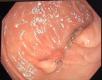

Introduction: Transanal minimally invasive surgery (TAMIS) is a valuable surgical option for removal of rectal polyps and early rectal cancers. A potential complication of this technique is abdominal entry if the lesion is located above the peritoneal reflection. We present the first case series describing the use of a laparoscopic stapling device to remove a sessile lesion, and seal the resulting defect simultaneously with full thickness excision of the rectal lesion, avoiding abdominal entry.

Presentation of cases: Five patients with rectal lesions between 8 and 14 cm from the anal verge are described in this case series. Each underwent a stapled-TAMIS procedure as the lesion was suspected to be above the peritoneal reflection. The goal specimen was achieved in each procedure.